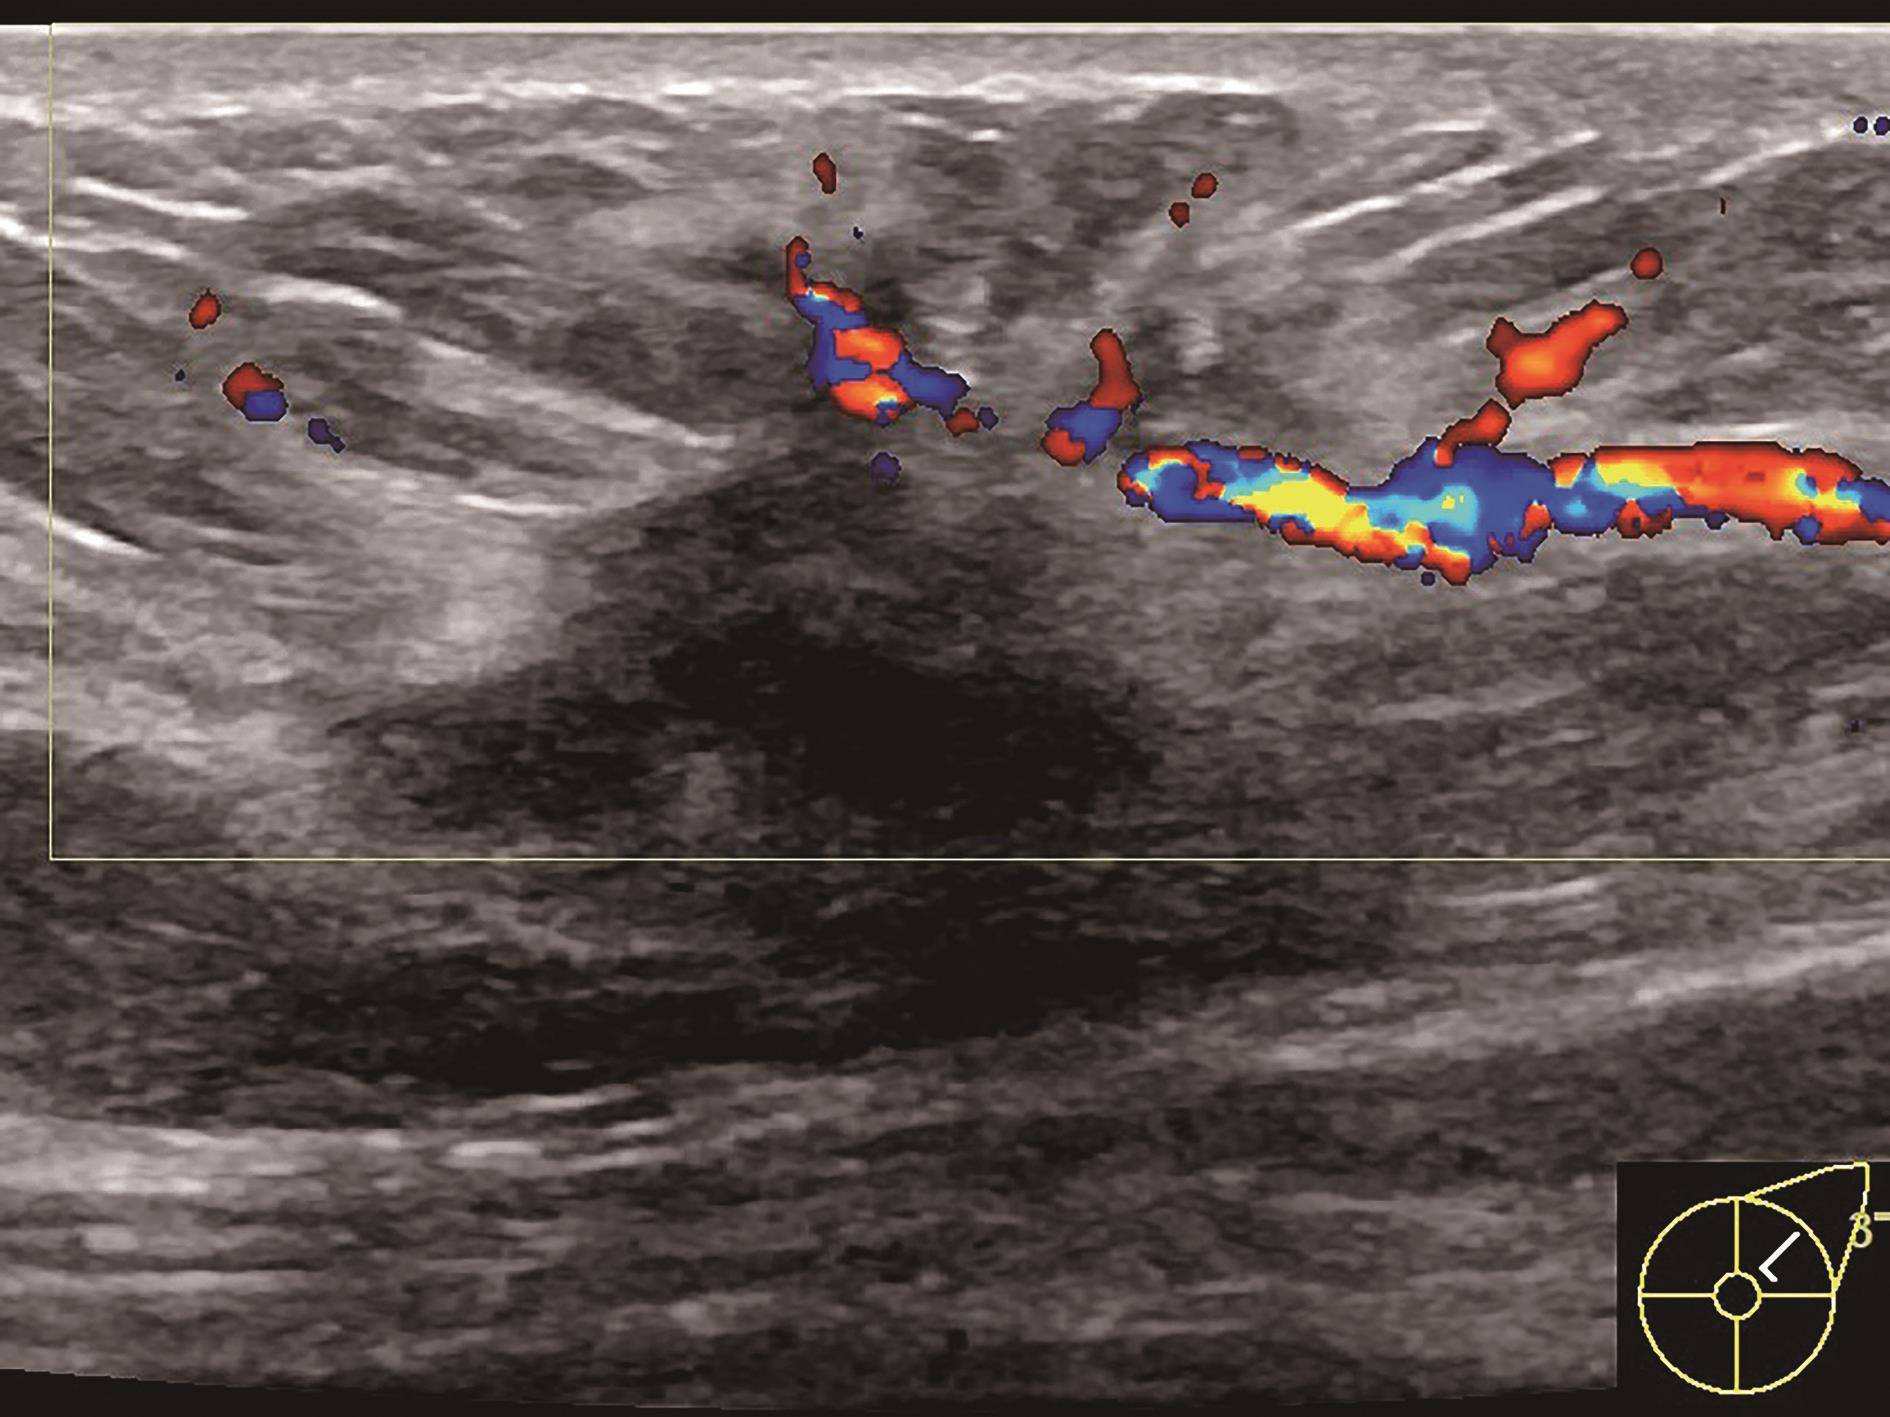

图2-2-1 确定造影病灶

A.病灶二维图像;B、C.病灶CDFI图像;D.同侧腋窝淋巴结情况;E.病灶弹性成像图像